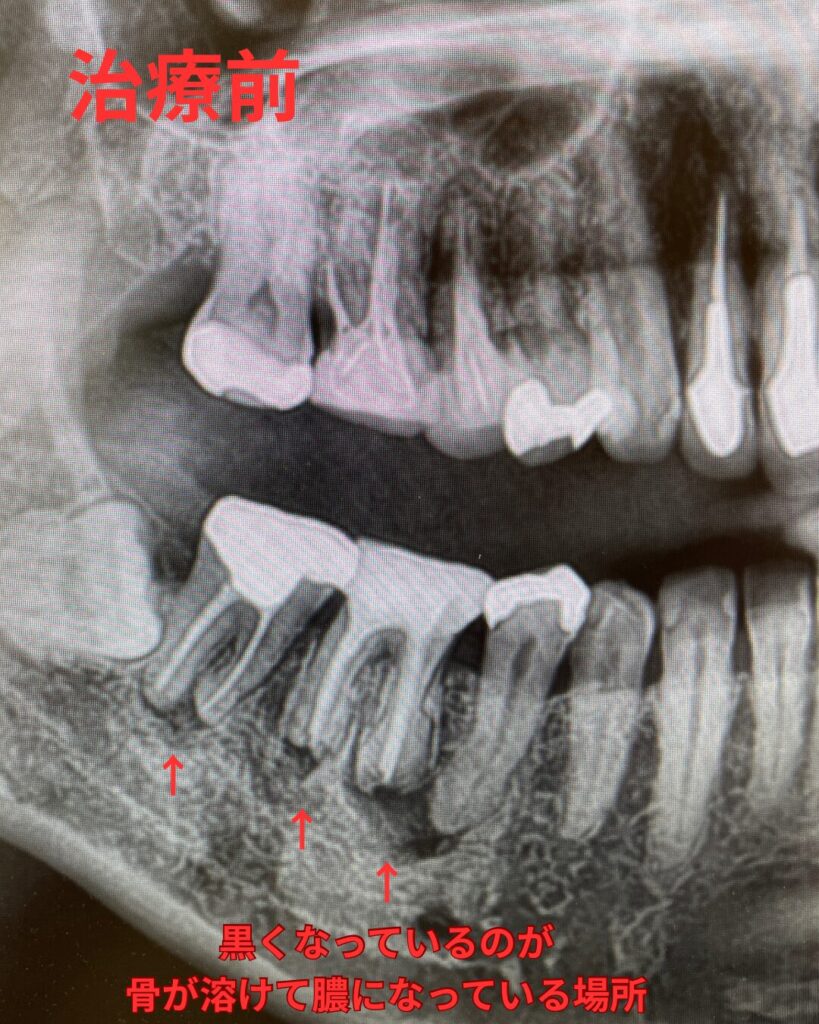

レントゲンの治療前後の比較

精密根管治療前後のレントゲン写真です。

右上の奥歯2本に強い自発痛があり、レントゲンでの所見も根尖部に透過像(陰影)を認めます。打診も強く早急な治療が必要でした。ご本人様は保険での歯科治療は望まれておらず、費用がかかったとしてもちゃんと治したいとご希望されたため、詳細なCTを撮影しました。第2小臼歯と第1大臼歯の現状を説明させて頂き、どちらも根管治療のやり直しと、大臼歯に関しては未治療根管があり、そちらが中で腐り強い炎症を引き起こしていると考えられることをお伝えしています。